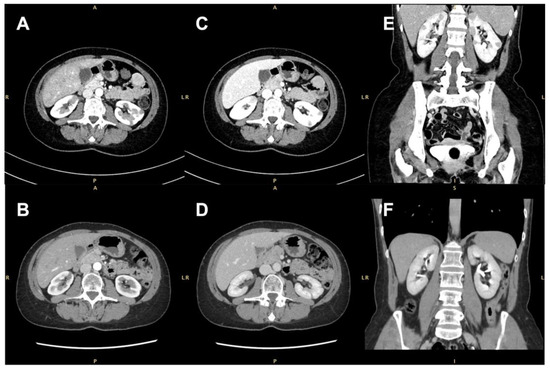

| Author | Sex/Age (y) | Extra-Renal Organ Involvement | ANCA | Kidney Tests | Imaging | Localisation | Biopsy | Kidney Removal | Histology | Treatment | Outcome |

|---|---|---|---|---|---|---|---|---|---|---|---|

| Tiwari [10] | F/60 | ENT, eye | MPO | Normal | US, CECT, PET | Unilateral | Yes | No | Granuloma | MTX | Remission |

| Maguire [11] | F/27 | ENT, lung | PR3 | NA | Renal arteriography | Unilateral | NA | Partial | Granuloma/Vasculitis | CYC | Remission |

| Schapira [12] | M/45 | ENT, lung | NA | UP | Gallium scan, US | Unilateral | No | Partial | Granuloma/Vasculitis | CYC | Remission |

| Schydlowsky [13] | M/47 | ENT, lung | Positive | Normal | US, CECT | Unilateral | No | Radical | Granuloma/Vasculitis | CYC | Remission |

| Smith [14] | F/52 | Eye | NA | WBCs | US, CT | Unilateral | No | Radical | Granuloma/Vasculitis | AZA | Remission |

| Boubenider [15] | F/45 | ENT, skin | PR3 | Renal failure, RBCs, UP | US, CT | Unilateral | Yes | Radical | Granuloma/Vasculitis | None | ESRD |

| Fairbanks [16] | M/68 | ENT, lung | MPO | Normal | CECT | Unilateral | Yes | No | Granuloma/Vasculitis | MTX | Remission |

| Dufour [17] | M/70 | ENT, PNS, lung | MPO | Renal failure | CT | Unilateral | No | Radical | Granuloma/Vasculitis | CYC | Relapsing disease |

| Dufour [17] | M/67 | MSK, lung, CNS | PR3 | Renal failure | CT | Unilateral | NA | No | NA | CYC | Death |

| Thomas [18] | F/48 | ENT, PNS, eye | NA | Renal failure | IVU, CT | Unilateral | Yes | Radical | Granuloma/Vasculitis | CYC | Remission |

| Verswijvel [19] | M/24 | ENT, spleen | PR3 | Renal failure, RBCs | US, CECT, MRI | Unilateral | Yes | No | Vasculitis | CYC | Remission |

| Carazo [20] | M/29 | Eye | PR3 | Normal | US, IVU, CECT | Bilateral | Yes | Radical | Granuloma/Vasculitis | CYC | Relapsing disease |

| Kapoor [21] | M/22 | - | PR3 | Renal failure, RBCs, UP | US, MRI | Bilateral | Yes | No | Vasculitis | - | ESRD |

| Leung [22] | M/66 | ENT, skin | MPO | Normal | US, CT | Bilateral | Yes | No | Granuloma | MTX | Remission |

| D’Hauwe [23] | F/14 | ENT, MSK | Negative | WBCs | US, CECT | Unilateral | Yes | No | Granuloma | RTX+MTX | Remission |

| Krambeck [24] | M/61 | ENT, CNS | Negative | Normal | CECT | Unilateral | No | Partial | Granuloma | AZA | Remission |

| Vandergheynst [25] | M/32 | PNS | PR3 | UP | CT | Unilateral | Yes | Partial | Granuloma/Vasculitis | CYC | Remission |

| Vandergheynst [26] | F/23 | ENT, skin, endocrine system | MPO | Normal | PET, CEUS | Bilateral | Yes | No | Granuloma/Vasculitis | RTX | Remission |

| Sichani [27] | F/22 | ENT, lung, DAH | Positive | UP, RBCs | US, CECT | Unilateral | Yes | No | Granuloma/Vasculitis | - | Death |

| Negi [28] | M/40 | ENT | PR3 | Renal failure | CT | Bilateral | No | No | NA | NA | Remission |

| Lo Gullo [29] | M/38 | ENT, lung | PR3 | Normal | US, CECT, PET | Unilateral | Yes | No | Granuloma | RTX | Remission |

| Frigui [30] | F/59 | ENT, eye | PR3 | UP | US, CECT | Bilateral | Yes | No | Granuloma/Vasculitis | CYC | Remission |

| Xu [31] | M/55 | - | PR3 | RBCs | CT | Unilateral | No | Radical | Vasculitis | NA | Remission |

| Roussou [32] | F/72 | ENT | MPO | Normal | CECT, MRI | Unilateral | No | Radical | Granuloma/Vasculitis | CYC | Remission |

| Ahmed [33] | F/28 | Lung | PR3 | RBCs | US, CT | Bilateral | Yes | No | Granuloma/Vasculitis | CYC | Remission |

| Ward [34] | F/48 | ENT, CNS, lung | PR3 | NA | CT | Unilateral | Yes | Radical | Granuloma/Vasculitis | CYC+RTX | Remission |

| Yamamoto [35] | M/60 | - | MPO | Normal | CECT, MRI | Unilateral | Yes | Radical | Granuloma/Vasculitis | - | Remission |

| Fu [36] | F/33 | ENT | Negative | Normal | US, PET | Bilateral | Yes | No | Granuloma/Vasculitis | CYC | Remission |

| Higashihara [37] | F/75 | - | Negative | Renal failure | CECT | Unilateral | No | Radical | Granuloma/Vasculitis | - | Remission |

| Dai [38] | M/32 | ENT, lung | PR3 | Normal | MRI, PET | Unilateral | Yes | No | Granuloma | CYC | Remission |

| Guo [39] | F/71 | Lung, eye | PR3 | Normal | CT | Bilateral | Yes | No | Granuloma | RTX | Remission |

| Kumar [40] | F/27 | ENT | PR3 | Normal | US, CECT, IVU | Unilateral | Yes | No | Granuloma | RTX | Remission |

| Reeders [41] | M/46 | Lung, skin, MSK | PR3 | Renal failure | CT | Unilateral | No | Radical | Granuloma/Vasculitis | RTX+CYC | Remission |

| Villa-Forte [42] | M/45 | ENT, lung | NA | NA | NA | Unilateral | No | Radical | Granuloma/Vasculitis | CYC | ESRD |

| Boncoraglio [43] | M/47 | ENT | PR3 | Renal failure, RBCs, UP | US, CT, MRI | Unilateral | No | Partial | Granuloma/Vasculitis | RTX | Remission |

| Abudaff [44] | M/20 | ENT | PR3 | Renal failure, RBCs, UP | US, CT | Unilateral | Yes | No | Vasculitis | RTX | Remission |

| Bicakcigil [45] | F/47 | ENT, breast, spleen | NA | NA | CT | Bilateral | Yes | No | NA | CYC | Remission |

| Gregorini [46] | M/46 | ENT, CNS | PR3 | Normal | CT | Unilateral | Yes | No | Granuloma | RTX+CYC | Remission |

| Kaikoi [47] | F/76 | ENT, eye | PR3 | Minimal UP | CECT | Unilateral | Yes | No | Granuloma/Vasculitis | CYC | Remission |

| Nketiah Sarpong [48] | M/57 | Lung, DAH | PR3 | Renal failure, RBCs, UP | NA | Unilateral | Yes | No | Granuloma/Vasculitis | RTX | Remission |

| Ramasamy [49] | F/39 | NA | Negative | Renal failure | NA | Unilateral | No | Radical | Granuloma/Vasculitis | NA | ESRD |

| Varkala [50] | M/22 | Lung, DAH, heart, skin | PR3 | Renal failure, RBCs, WBCs, granular casts | CECT | Unilateral | Yes | No | Vasculitis | CYC | Remission |

| Present case | F/49 | - | PR3 | Normal | US, CECT, PET-MR | Bilateral | Yes | No | Granuloma | RTX | Remission |